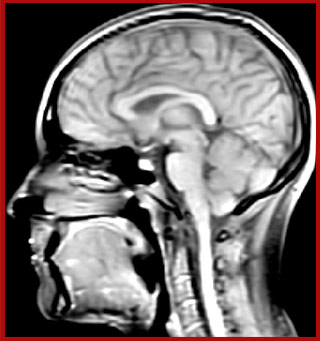

For Dr. Kolind, the Elition excels in advanced neuroimaging for two main reasons. “It's image quality and access to so many different imaging parameters. We’re involved in several multi-center studies, and we can always easily identify the images that came from our Elition scanner, because they are just so beautiful – even though it seems like we’ve set our parameters similarly to other study participants. And as a physicist, being able to do many things, for instance to push resolution and save time, is really helpful.”

He says the accelerated scanning is achieved via the use of Compressed SENSE and MultiBand SENSE. “We can use Compressed SENSE acceleration factors of about 10 on a 3D FLAIR for instance, which is quite remarkable compared with what we saw with the Achieva. With 3D FLAIR, we can push the spatial resolution to 0.3 cubic mm and it works. Previously, our 3D FLAIR scans lasted about 8 minutes, but now with Elition they are five minutes. The SNR is also visibly better. Our SWI and QSM scans look fantastic. Also, since a lot of neuroimaging is EPI based, using the MultiBand SENSE technique can increase temporal resolution and make it possible to run complicated DTI scans relatively quickly.”

Sagittal 3D FLAIR with 0.3 mm3 voxel volume acquired in 5:12 min. using Compressed SENSE showing a (juxta)cortical MS lesion.